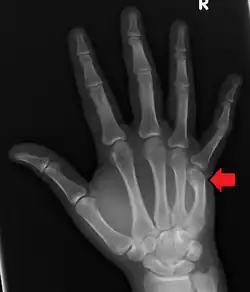

| Boxer's fracture of the 5th metacarpal head from punching a wall | |

Classically, it occurs after a person hits an object with a closed fist.[3] The knuckle is then bent towards the palm of the hand.[3] Diagnosis is generally suspected based on symptoms and confirmed with X-rays.[3]

Diagnosis by a doctor's examination is the most common, often confirmed by x-rays. X-ray is used to display the fracture and the angulations of the fracture. A CT scan may be done in very rare cases to provide a more detailed picture.